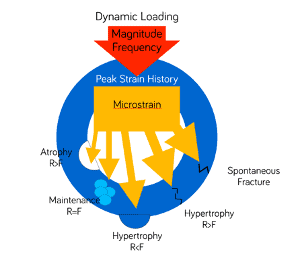

Nobody likes pressure, but mechanosensitive tissue like bone has actually evolved with primary objective to respond to pressure. The classic work of Frost (2) on the Wolf’s law has shown that forces of certain intensity will actually have an anabolic effect on the bone, while it is only when forces exceed a certain threshold that they become detrimental. (Does this sound a bit like the common “clinical wisdom” that some insertion torque is good, but too much might be more trouble than benefit?)

Although Wolf was able to calculate this threshold of strain for long bones in humans, we really know very little of how this fundamental principle would apply in the micro-structural environment of the complex alveolar ridge.

The actual bone response of different segments of the alveolar ridge to different levels of forces applied by an implant remains unknown. One can only assume that force beyond the elastic modulus of the bone will cause plastic deformation, commonly known as fracture and possibly necrosis, if the bone segment is squeezed beyond its repairability or deprived of vascularization